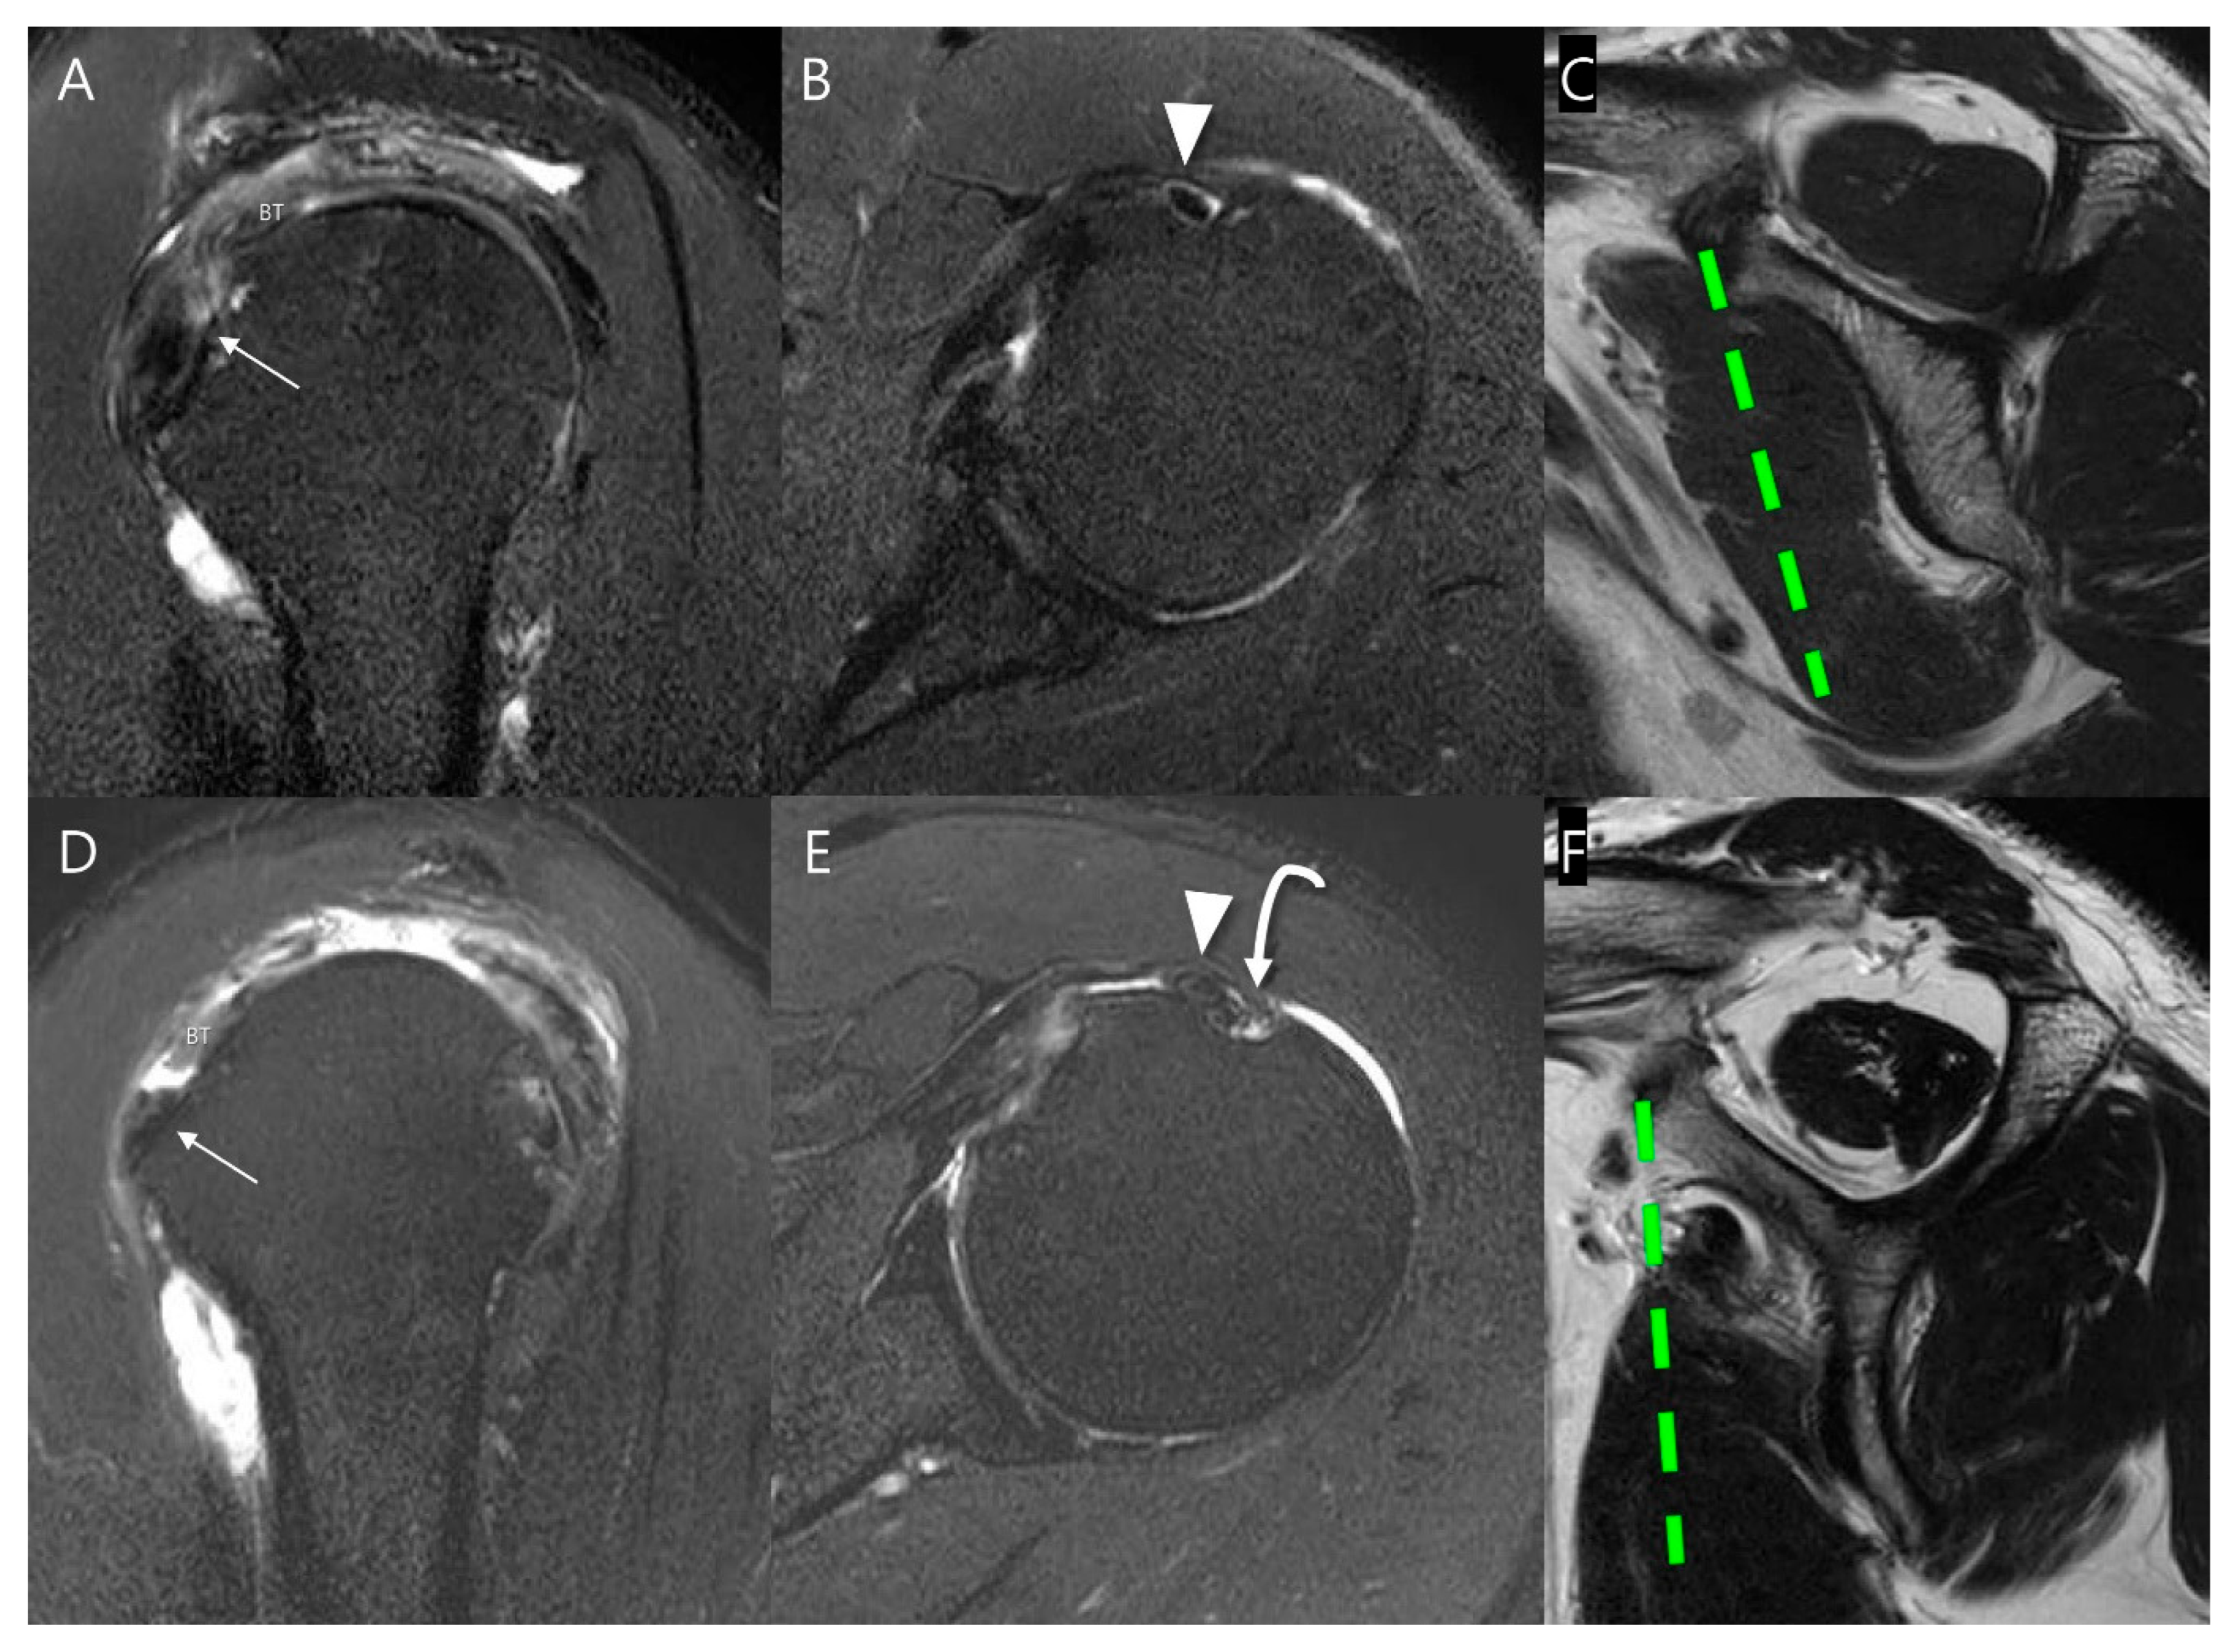

Figure 8.

Representative MR images of Yoo type IIA (A–C) and IIB (D–F) subscapularis tendon (SSC) tears: (A) T2-weighted oblique sagittal fat-suppressed image in a patient with a Yoo type IIA lesion demonstrates a partial thickness tear of the SSC with ≤50% detachment from the first facet (arrow). (B) T2-weighted oblique axial fat-suppressed image shows an intact long head of the biceps tendon (LHBT, arrowhead) in the bicipital groove. (C) The T2-weighted oblique sagittal image shows no muscle atrophy. (D) T2-weighted oblique sagittal fat-suppressed image in a patient with a Yoo type IIB lesion demonstrates a partial thickness tear of the SSC > 50% detachment from the first facet (arrow). (E) T2-weighted oblique axial fat-suppressed image shows subluxation of LHBT (arrowhead) from the bicipital groove (curved arrow). (F) T2-weighted oblique sagittal image shows moderate muscle atrophy, especially in the upper half. BT, biceps tendon.